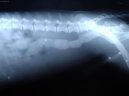

:  > Cizí tělesa v zažívacím traktu a kostní trus. (Veterinární zákroky) Cizí tělesa v zažívacím traktu a kostní trus. (Veterinární zákroky) - Cizí tělesa jsou jednoduše takové předměty v zažívacím aparátu, které tam zkrátka nepatří.